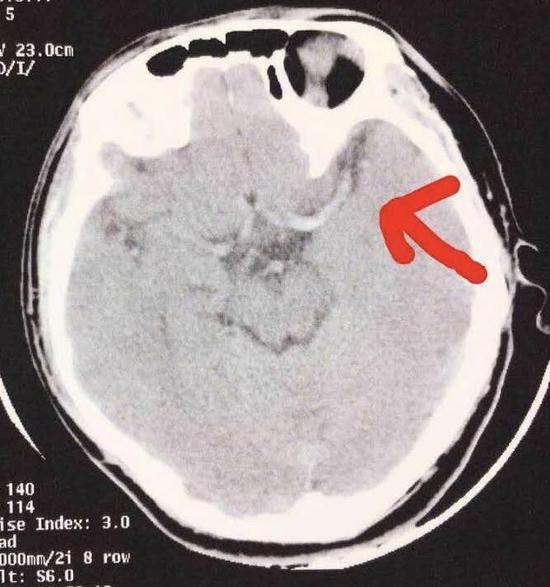

这样的状态持续了大概1个月。一天清早,小斌妈妈刚到单位,就接到丈夫打来电话说儿子晕倒了。小斌左侧身体无法动弹,瘫坐在地上,口角歪斜。送到医院做完检查,结果让夫妻俩觉得不可思议——孩子脑中风了!

广西江滨医院中医脑病科主任利春红告诉记者,小斌此前饮食、作息严重不规律,摄入不足、休息不够,会导致血压降低,时间长了,脑组织缺血缺氧,就会出现脑中风。